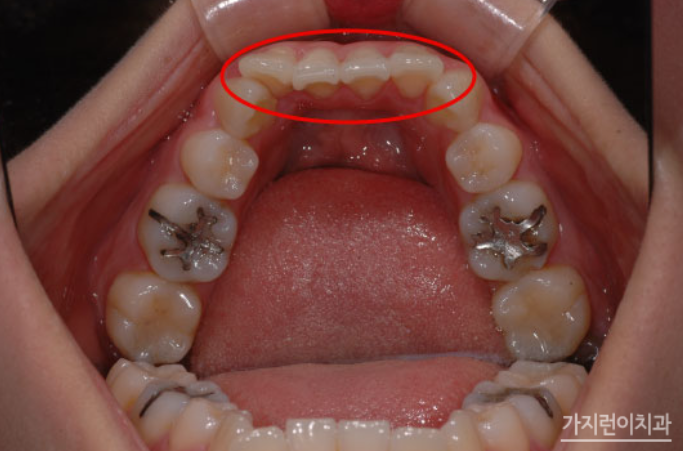

치아교정은 돌출입, 덧니, 주걱턱, 벌어진 치아로 인해 외적인 스트레스를 받는 사람들에게는 심미적인 관점에서 치아교정이 하나의 방법이 될 수 있는데요. 치아교정은 보통 2년이라는 시간이 소요되다 보니 신중에 신중을 기해 시작을 하게 됩니다. 그런데 길다면 길고 짧다면 짧은 2년의 시간 동안 치아교정을 했는데 이런저런 문제로 발생한다면 속상하지 않을 수 없겠죠. 첫 치아교정부터 제대로 교정해서 재교정이 필요하지 않으면 좋겠지만 여러 가지 이유로 재교정이 꼭 필요한 경우라면 어떤 경우가 있을까요?

- 유지장치를 잘 안 하거나 유지장치가 떨어진 채로 방치하다가 문제가 생긴 경우

- 다시 치아가 벌어진 경우

아무래도 나이가 들수록 잇몸이 약해질 수밖에 없는데요. 치아의 뿌리를 잡고 있는 뼈가 많이 내려가서 치아를 안전하게 잡아주는 능력이 떨어지다 보니 잇몸의 상태에 따라 재교정 가능 여부와 치료 범위를 결정되게 됩니다. 재교정 후에는 치아가 다시 틀어지지 않도록 유지장치를 잘 착용하고 정기 검진을 통해 치아와 잇몸 건강 관리를 잘 하는 것이 중요하겠죠.